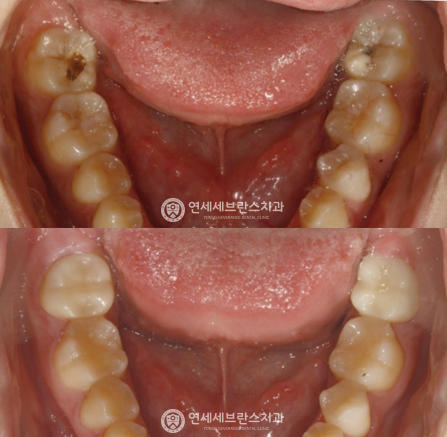

03

전악 임플란트

치아가 하나도 없거나 심각한 구강질환을 앓고 있어도

전악 보철을 제작, 임플란트를 치조골에 식립해

기능적, 심미적으로 자연치아와 가장 유사한 수준으로 재현이 가능합니다.